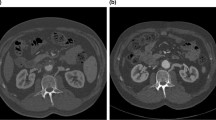

CT imaging showed a notable LRV compression by RRA in a 58-year-old male with membranous nephropathy. The ending segment of LRV was compressed by the proximal RRA (green arrows in a–c), arising at a 10:30 clockwise direction (c). The narrowest site was at the compression site (white arrowheads in a–c and e), and the maximum-to-minimum area ratio was calculated as 2.93 depending on the measurements on a and b (circled green lines). The dilated lumber veins could be recognized (d, f). IVC, inferior vena cava; LRV, left renal vein; RRA, right renal artery; CT, computed tomography. Long-shafted white arrows (without text), IVC; paired arrowheads, collateral veins

Relevant parameters concerning the RRA-sourced compression

After excluding other anatomical compression factors, we analyzed the relationship between the RRA compression and multiple parameters in the Renal and Non-renal groups, with 22 patients in each group (Table 1). There was no gender or age difference between the Compressed and Non-compressed subgroups. The narrowest part of LRV had a high incidence at the ending segment before its confluence into IVC (77.27% Renal and 86.36% Non-renal, respectively, no significance). There was no statistical difference in the narrowest site classification between the groups and subgroups, and no cases were found with the narrowest site at the LRV Segment 1. The maximum-to-minimum ratios of the LRV transectional areas in the Compressed subgroups were significantly higher than that of the corresponding Non-compressed subgroups in both groups (3.09 ± 1.29 vs. 1.82 ± 0.23, p < 0.001; and 4.30 ± 2.65 vs. 2.12 ± 0.55, p = 0.006 in the Renal and Non-renal groups, respectively).

Previous studies mostly measured the anteroposterior diameter of the LRV lumen on axial CT images to evaluate the changes in the LRV caliber caused by compression [4, 18,19,20]. The area measurement method adopted in the present study [21, 22] seems capable of evaluating the caliber sizes more accurately because it considers the possibility of a small anteroposterior distance with a disproportionately sizeable superoinferior distance (Figs. 1a, b, e, f, 2c), which is frequently seen in our patient cohorts (Online Resource 4). After excluding other sources of compression, we found that the distal segments of the LRVs compressed by RRAs have a significantly larger lumen area than those of non-compressed veins, suggesting that this compression may affect the venous drainage of LRV.